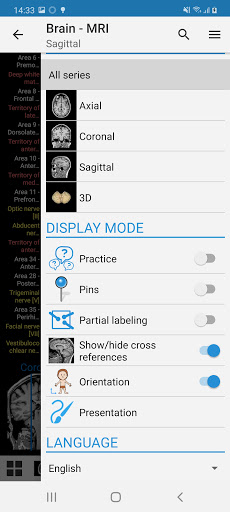

-You can now use Facebook or Google to sign in to the app.-The practice mode is now available in the lateral panel while viewing a module. (Structures names will be replaced with numbers and you can tap on it to display them)-Redesign and new nomenclature of coronary arteries for the module of the coronary angiogram and coronary CT. The anatomical terms are now more adapted to angiographic nomenclature and to cardiac imaging practice.-Fixed small bugs